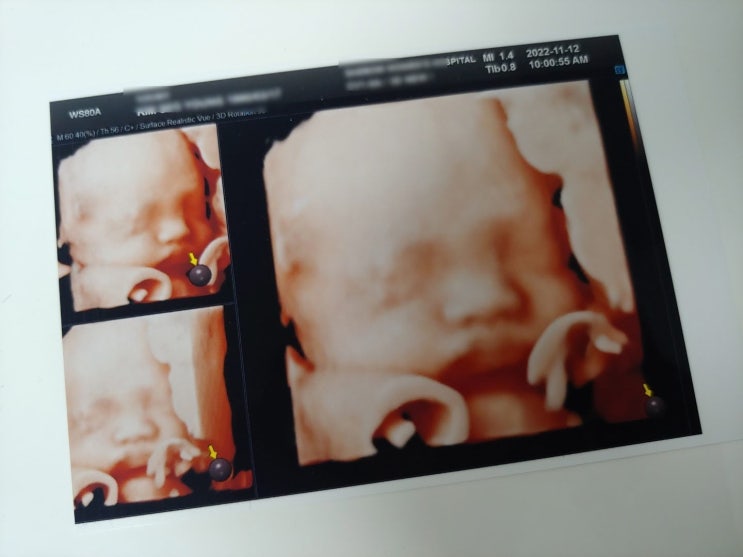

임신 28주차 - 4D 입체초음파, 집에서 찍은 주수사진

#임신8개월 #경산모 #둘째임신 #임신28주차 #입체초음파 임신 28주 6일차에 똑똑이를 만나러 갔다 토요일 ...